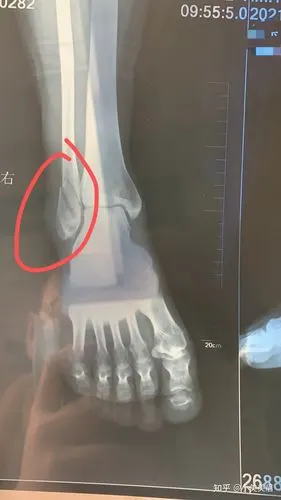

脚外踝骨折记录